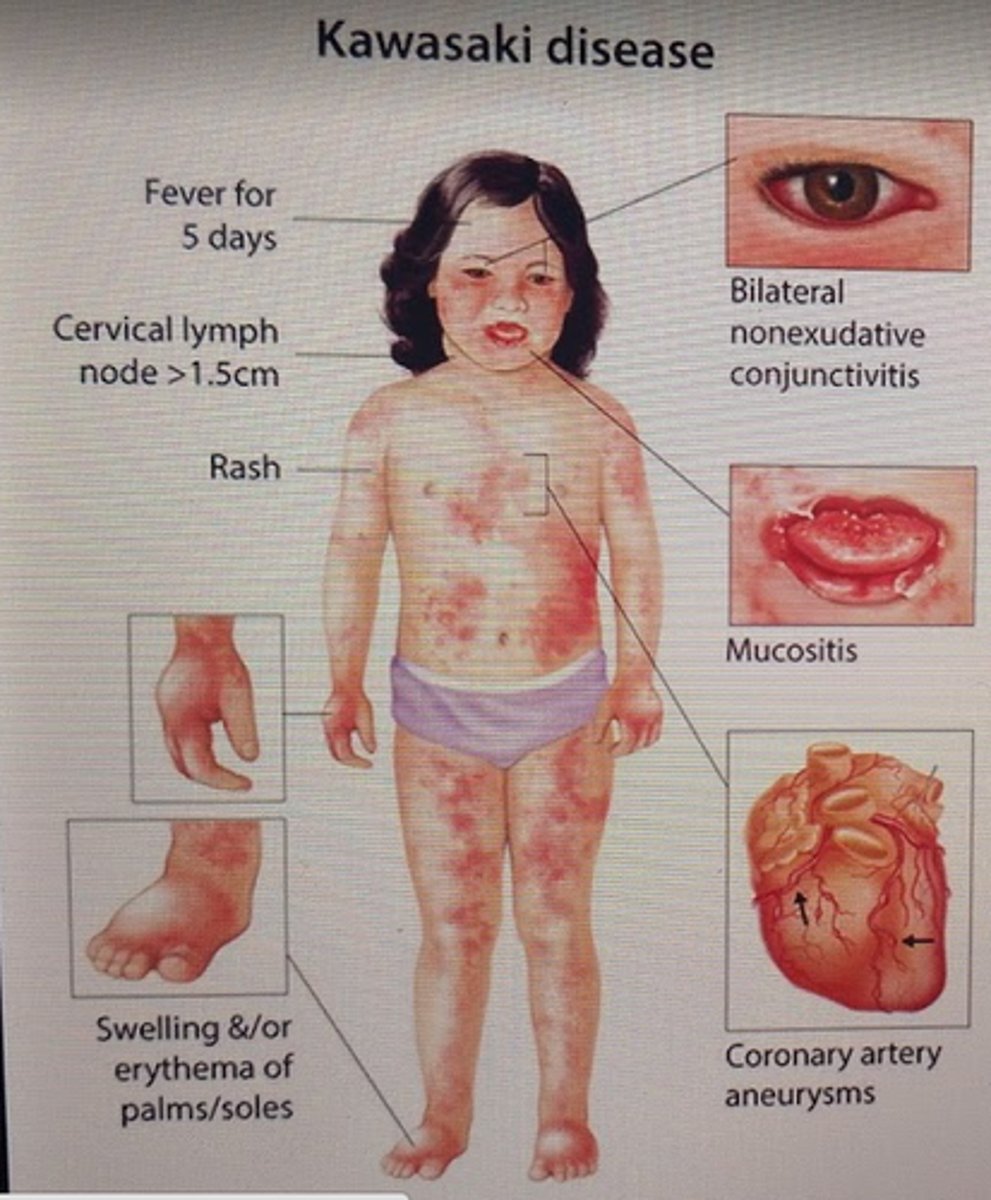

Cervical lymphadenopathy, desquamating rash on palms and soles, coronary aneurysms, red conjuctivae, and strawberry tongue

Kawasaki disease (treat with IVIG and aspirin which inhibits TXA2)

"Strawberry tongue"

Scarlet fever, Kawasaki disease